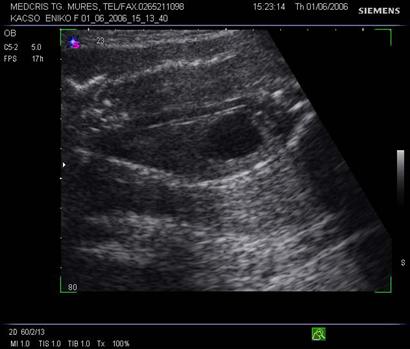

Fig. nr. 280. Formatiune anecogena intrabdominala, posibil hidronefroza , la un fat cu anamnios, retard major de crestere intrauterina RCIU si presupus sindrom genetic

Fig. nr. 281. Acelasi fat cu anamnios si RCIU, cu os nazal relativ scurt